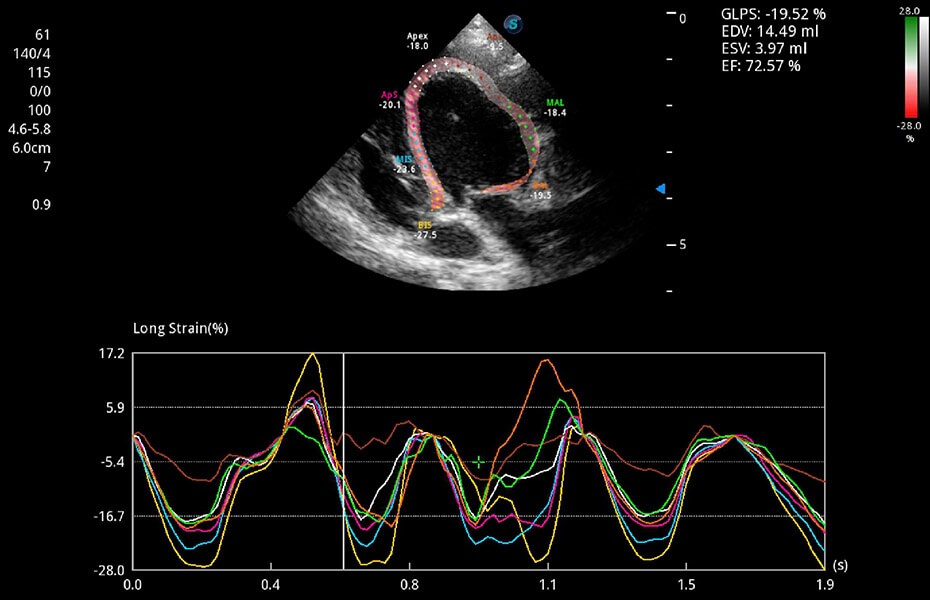

ProPet 60 作為一款高端臺(tái)式動(dòng)物超聲設(shè)備,為動(dòng)物醫(yī)生的日常診斷提供了一系列貼合動(dòng)物臨床需求、解決臨床實(shí)際問(wèn)題的高級(jí)成像功能。憑借全系列高清探頭,滿足醫(yī)生對(duì)腹部、心臟、生殖、淺表、肌骨等成像的所有需求,切實(shí)幫助您提升檢查效率,提高診斷信心。